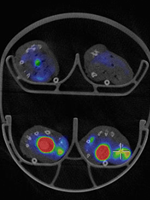

PET/CT-bild av möss (transversal vy) med tumörupptag av Fluor-18.

PET och SPECT-tekniken bygger på att man injicerar en liten mängd radioaktivt ämne i kroppen. Ämnet söker sig till det område i kroppen som forskarna vill studera, till exempel en tumör. Genom att mäta strålningen som ämnet avger kan man få en bild av tumörens storlek, form och hur mycket aktivitet som har tagits upp i tumören.

De nya PET- och SPECT-kamerorna, speciellt utformade för forskning på smådjur, erbjuder betydande förbättringar jämfört med tidigare system. Den höga upplösningen möjliggör visualisering av mindre detaljer och ger en mer precis bild av de fysiologiska processer som man studerar. Kameran är dessutom snabbare och kan avbilda flera djur samtidigt, vilket effektiviserar forskningen och sparar både tid och resurser i form av färre försöksdjur. Den ökade effektiviteten ger även ekonomiska fördelar för forskargrupperna. Dessutom har kameran en förbättrad användarvänlighet som underlättar forskarnas arbete.